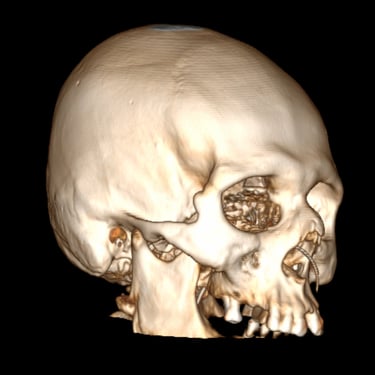

Hidrocefalia – Colocación de derivación ventriculoperitoneal (DVP).

La hidrocefalia es una condición neurológica causada por la acumulación anormal de líquido cefalorraquídeo dentro de los ventrículos cerebrales, lo que genera aumento de la presión intracraneal y deterioro neurológico progresivo. La colocación de una derivación ventrículoperitoneal (DVP) es el tratamiento quirúrgico más utilizado para controlar esta patología. Este sistema permite drenar el exceso de líquido desde el cerebro hacia la cavidad abdominal, donde se reabsorbe de manera segura. La intervención oportuna alivia los síntomas, previene daño cerebral y mejora la calidad de vida del paciente.